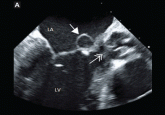

ArticleFever, dyspnea, and a new heart murmurAuthor:Lee Fong Ling, MBBS, MMedPublish date: September 1, 2013In cases of recurrent persistent fever and a new heart murmur, infective endocarditis must always be considered.Read More